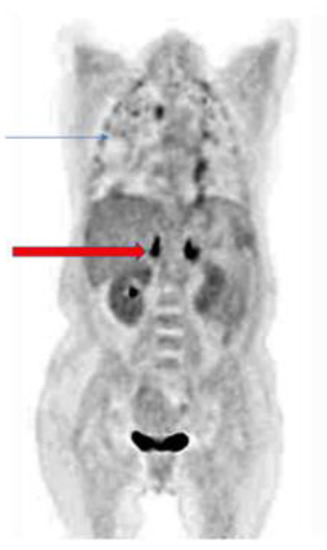

- Ankrah, A.O.; Span, L.F.R.; Klein, H.C.; de Jong, P.A.; Dierckx, R.A.J.O.; Kwee, T.C.; Sathekge, M.M.; Glaudemans, A.W.M.J. Role of FDG PET/CT in monitoring treatment response in patients with invasive fungal infections. Eur. J. Nucl. Med. Mol. Imaging 2019, 46, 174–183. [Google Scholar] [CrossRef] [PubMed]

- Douglas, A.P.; Thursky, K.A.; Worth, L.J.; Drummond, E.; Hogg, A.; Hicks, R.J.; Slavin, M.A. FDG PET/CT imaging in detecting and guiding management of invasive fungal infections: A retrospective comparison to conventional CT imaging. Eur. J. Nucl. Med. Mol. Imaging 2019, 46, 166–173. [Google Scholar] [CrossRef]

- Ankrah, A.O.; Creemers-Schild, D.; de Keizer, B.; Klein, H.C.; Dierckx, R.A.J.O.; Kwee, T.C.; Span, L.F.R.; de Jong, P.A.; Sathekge, M.M.; Glaudemans, A.W.J.M. The added value of [18F]FDG PET/CT in the management of invasive fungal infections. Diagnostics 2021, 11, 137. [Google Scholar] [CrossRef]